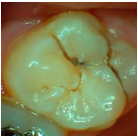

Over the past 20 years, the indication for resin sealant use on occlusal surfaces has changed. Previously, occlusal surfaces were sealed to prevent the development of carious lesions, and were called preventive sealants. In cases where sealants are placed over carious lesions, the term therapeutic sealants is more accurate. Today, sealants are primarily used for therapeutic purposes, aimed at arresting incipient active lesions (6,11,12. For this therapeutic use of sealants, it is essential to assess the extent and activity of the lesion. If the lesion is inactive (photos 1 and 2), treatment is likely unnecessary. However, if the lesion is active, sealant placement can be an excellent option for the patient 12.